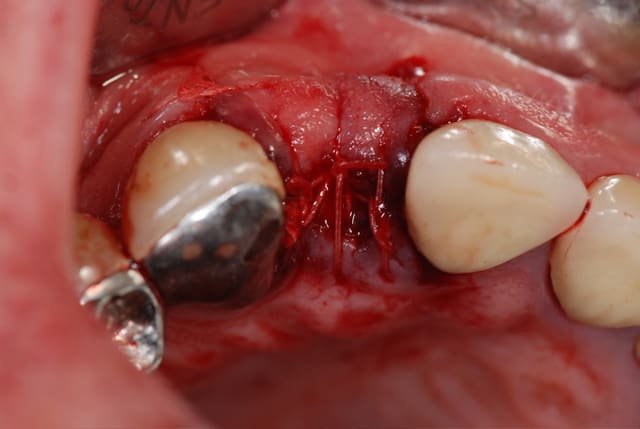

finalement, ça s'est terminé par une E. mais pas de I.I. ni de temporisation immédiate du tout malheureusement; par contre, pose de membrane et de ß TCP; voici les photos; ah oui, photo aussi d'une endo top de top (c'est pas moi, c'est pas moi!); l'extraction s'est faite avec un kit de piezo que l'on m'a prêté pour essai, c'est génial de chez génial, très très peu de délabrement, ostéotomie très fine, danger inexistant, je suis séduit

on voit sur la photo de l'alvéole vide en palatin le début de"trou" que j'ai fait, il faut se méfier du piezo quand même, c'est à la fois très sécurisant mais c'est aussi puissant, la preuve, il faut donc continuer à réfléchir, pfffff, et la suite arrive

après forage du puit en ø 3, j'ai testé le site et j'ai compris tout de suite que ça n'allait sans doute pas se passer comme d'habitude, le foret bougeait trop à 15 mm; j'ai quand même continué en ø 4 et mis le taraud pour voir; ça a bien bloqué mais j'étais sceptique; le problème, c'est que ça saignait aussi de façon anormale; j'ai donc décidé de soulever le lambeau en PE pour voir ce qui se passait....je n'ai pas été déçu; j'ai cureté le TG qui était externe à l'alvéole, j'aurais d'ailleurs pû y penser tout de suite en voyant la racine, et j'ai changé d'objectif : plus d'implant mais comblement seul; j'ai refermé avec le TCP et la membrane de collagène que j'ai quasiment intégralement recouverte par un lambeau d'épaisseur partielle; la membrane devrait s'exposer un peu mais ça se gère habituellement sans problème